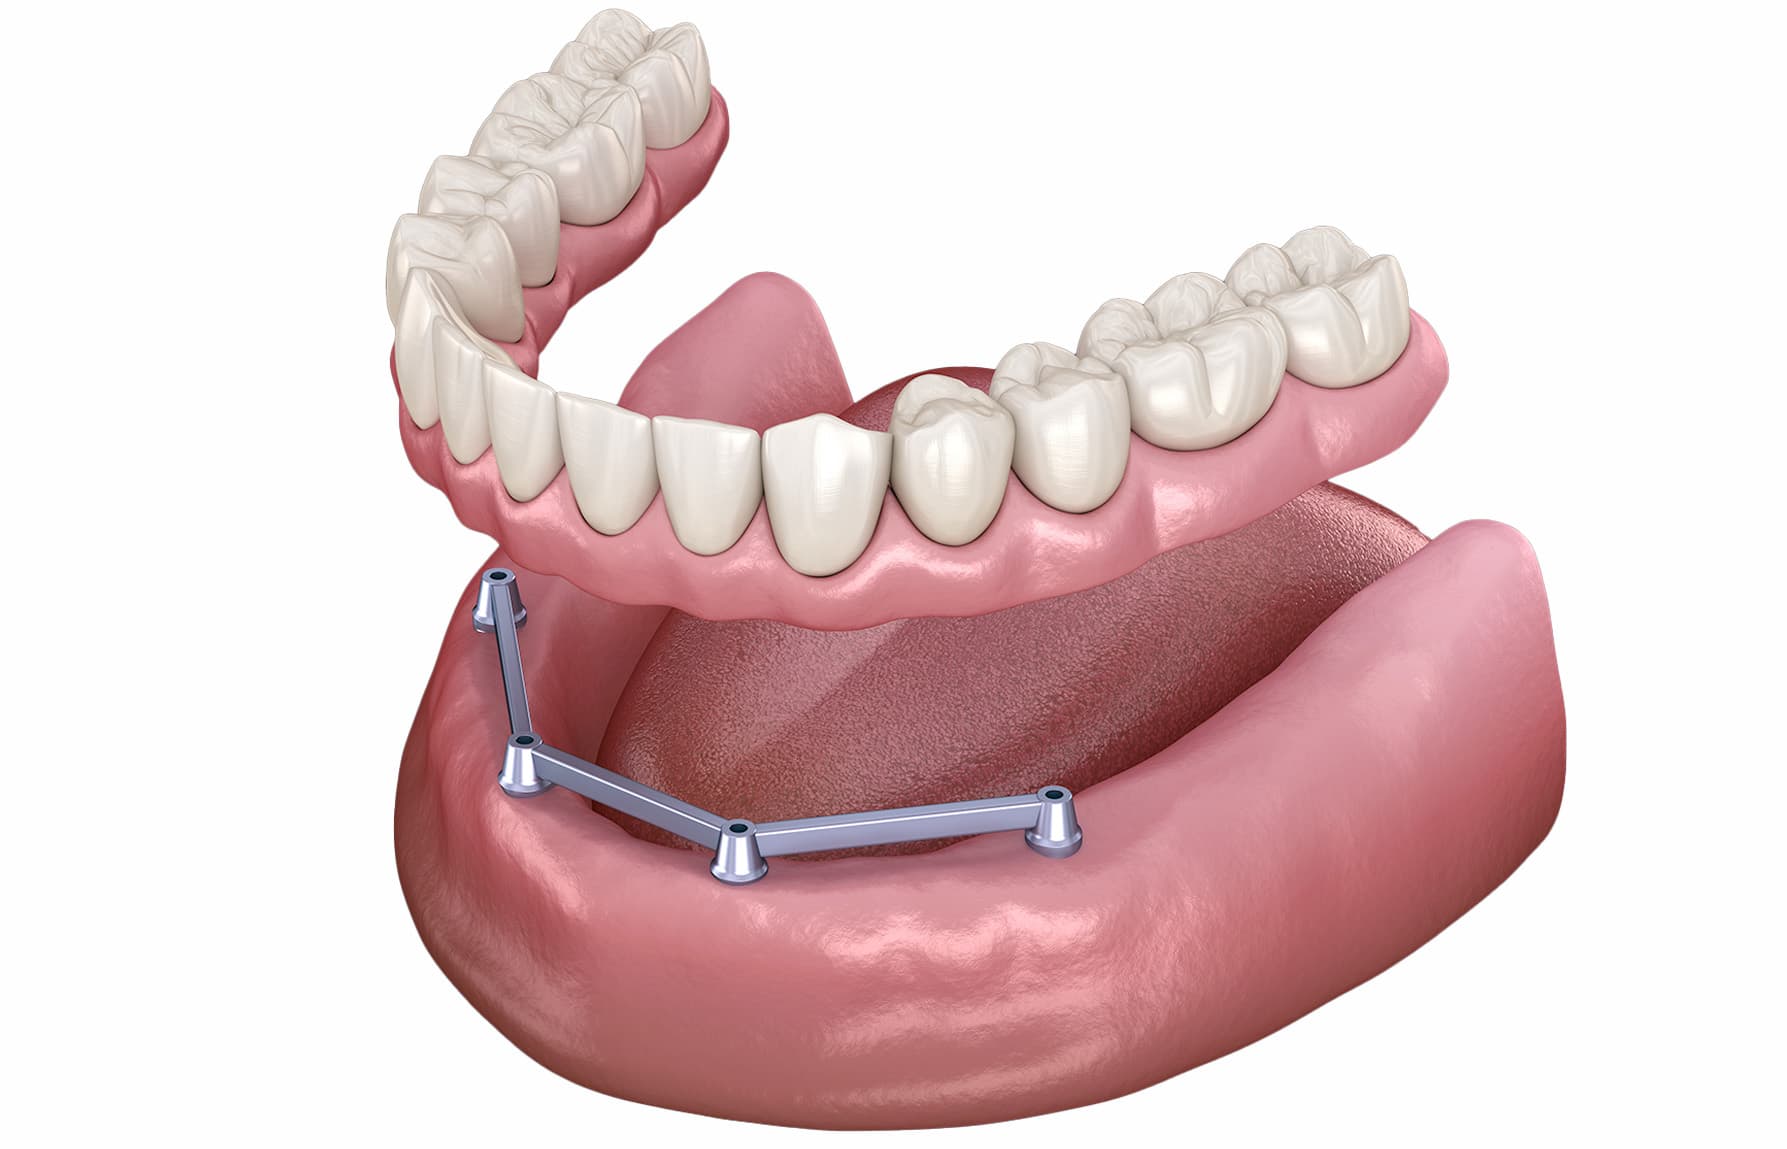

Stap 5 - Het plaatsen van de gebitsprothese

Tijdens deze behandelafspraak wordt uw nieuwe prothese geplaatst. Het maken van een passende prothese is maatwerk. Wij streven tot in de kleinste details, de hoogste kwaliteit na. Dit doen wij met succes, gezien onze talloze tevreden klanten. Toch kan het een enkele keer voorkomen dat een prothese, na de gebruikelijke gewenningsperiode, niet optimaal past. Dit kan leiden tot gevoelige plekken, of irritatie in de mond, omdat de prothese wat te krap zit of juist te ruim. Uiteraard kunnen onze tandprotheticus en tandtechnicus deze klachten altijd goed verhelpen.